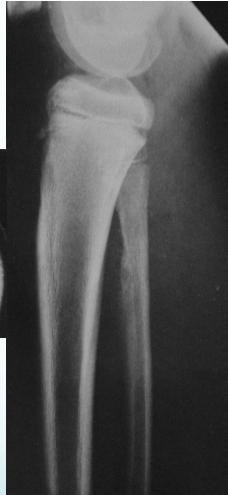

Ewing’s Sarcoma

- From bone marrow cells

- A round-cell tumor

- Age: 10-20 yrs.

- Tubular bone

- Tibia, fibula, clavicle

- Presentation:

- Throbbing pain

- Swelling

- Tenderness

- Hotness

- ESR raised

Source: Apley’s System of Orthop. And Fractures

Differential: Osteomyelitis ?